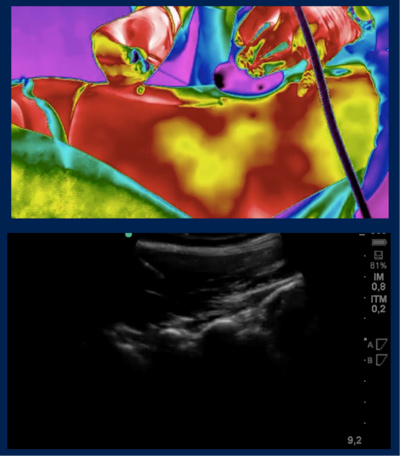

Os bloqueios diagnósticos são procedimentos minimamente invasivos realizados com precisão, guiados por algum método de imagem, normalmente usamos ultrassom, termografia infravermelha ou RX contínuo (radioscopia).

Esta técnica visa localizar de maneira mais efetiva a origem da dor, fazendo o que chamamos “mapa da dor”. A partir desta primeira intervenção, podemos definir o tratamento mais adequado e preciso para cada paciente.

Estes bloqueios são sempre guiados com técnicas de imagem, utilizamos ultrassom, termografia infravermelha ou radioscopia (RX em tempo real).

O bloqueio teste é realizado colocando anestésico local na articulação suspeita, confirmando assim o diagnóstico. Este procedimento deve ser sempre realizado guiado por imagem (ultrassom ou radioscopia) para garantir um resultado fidedigno.